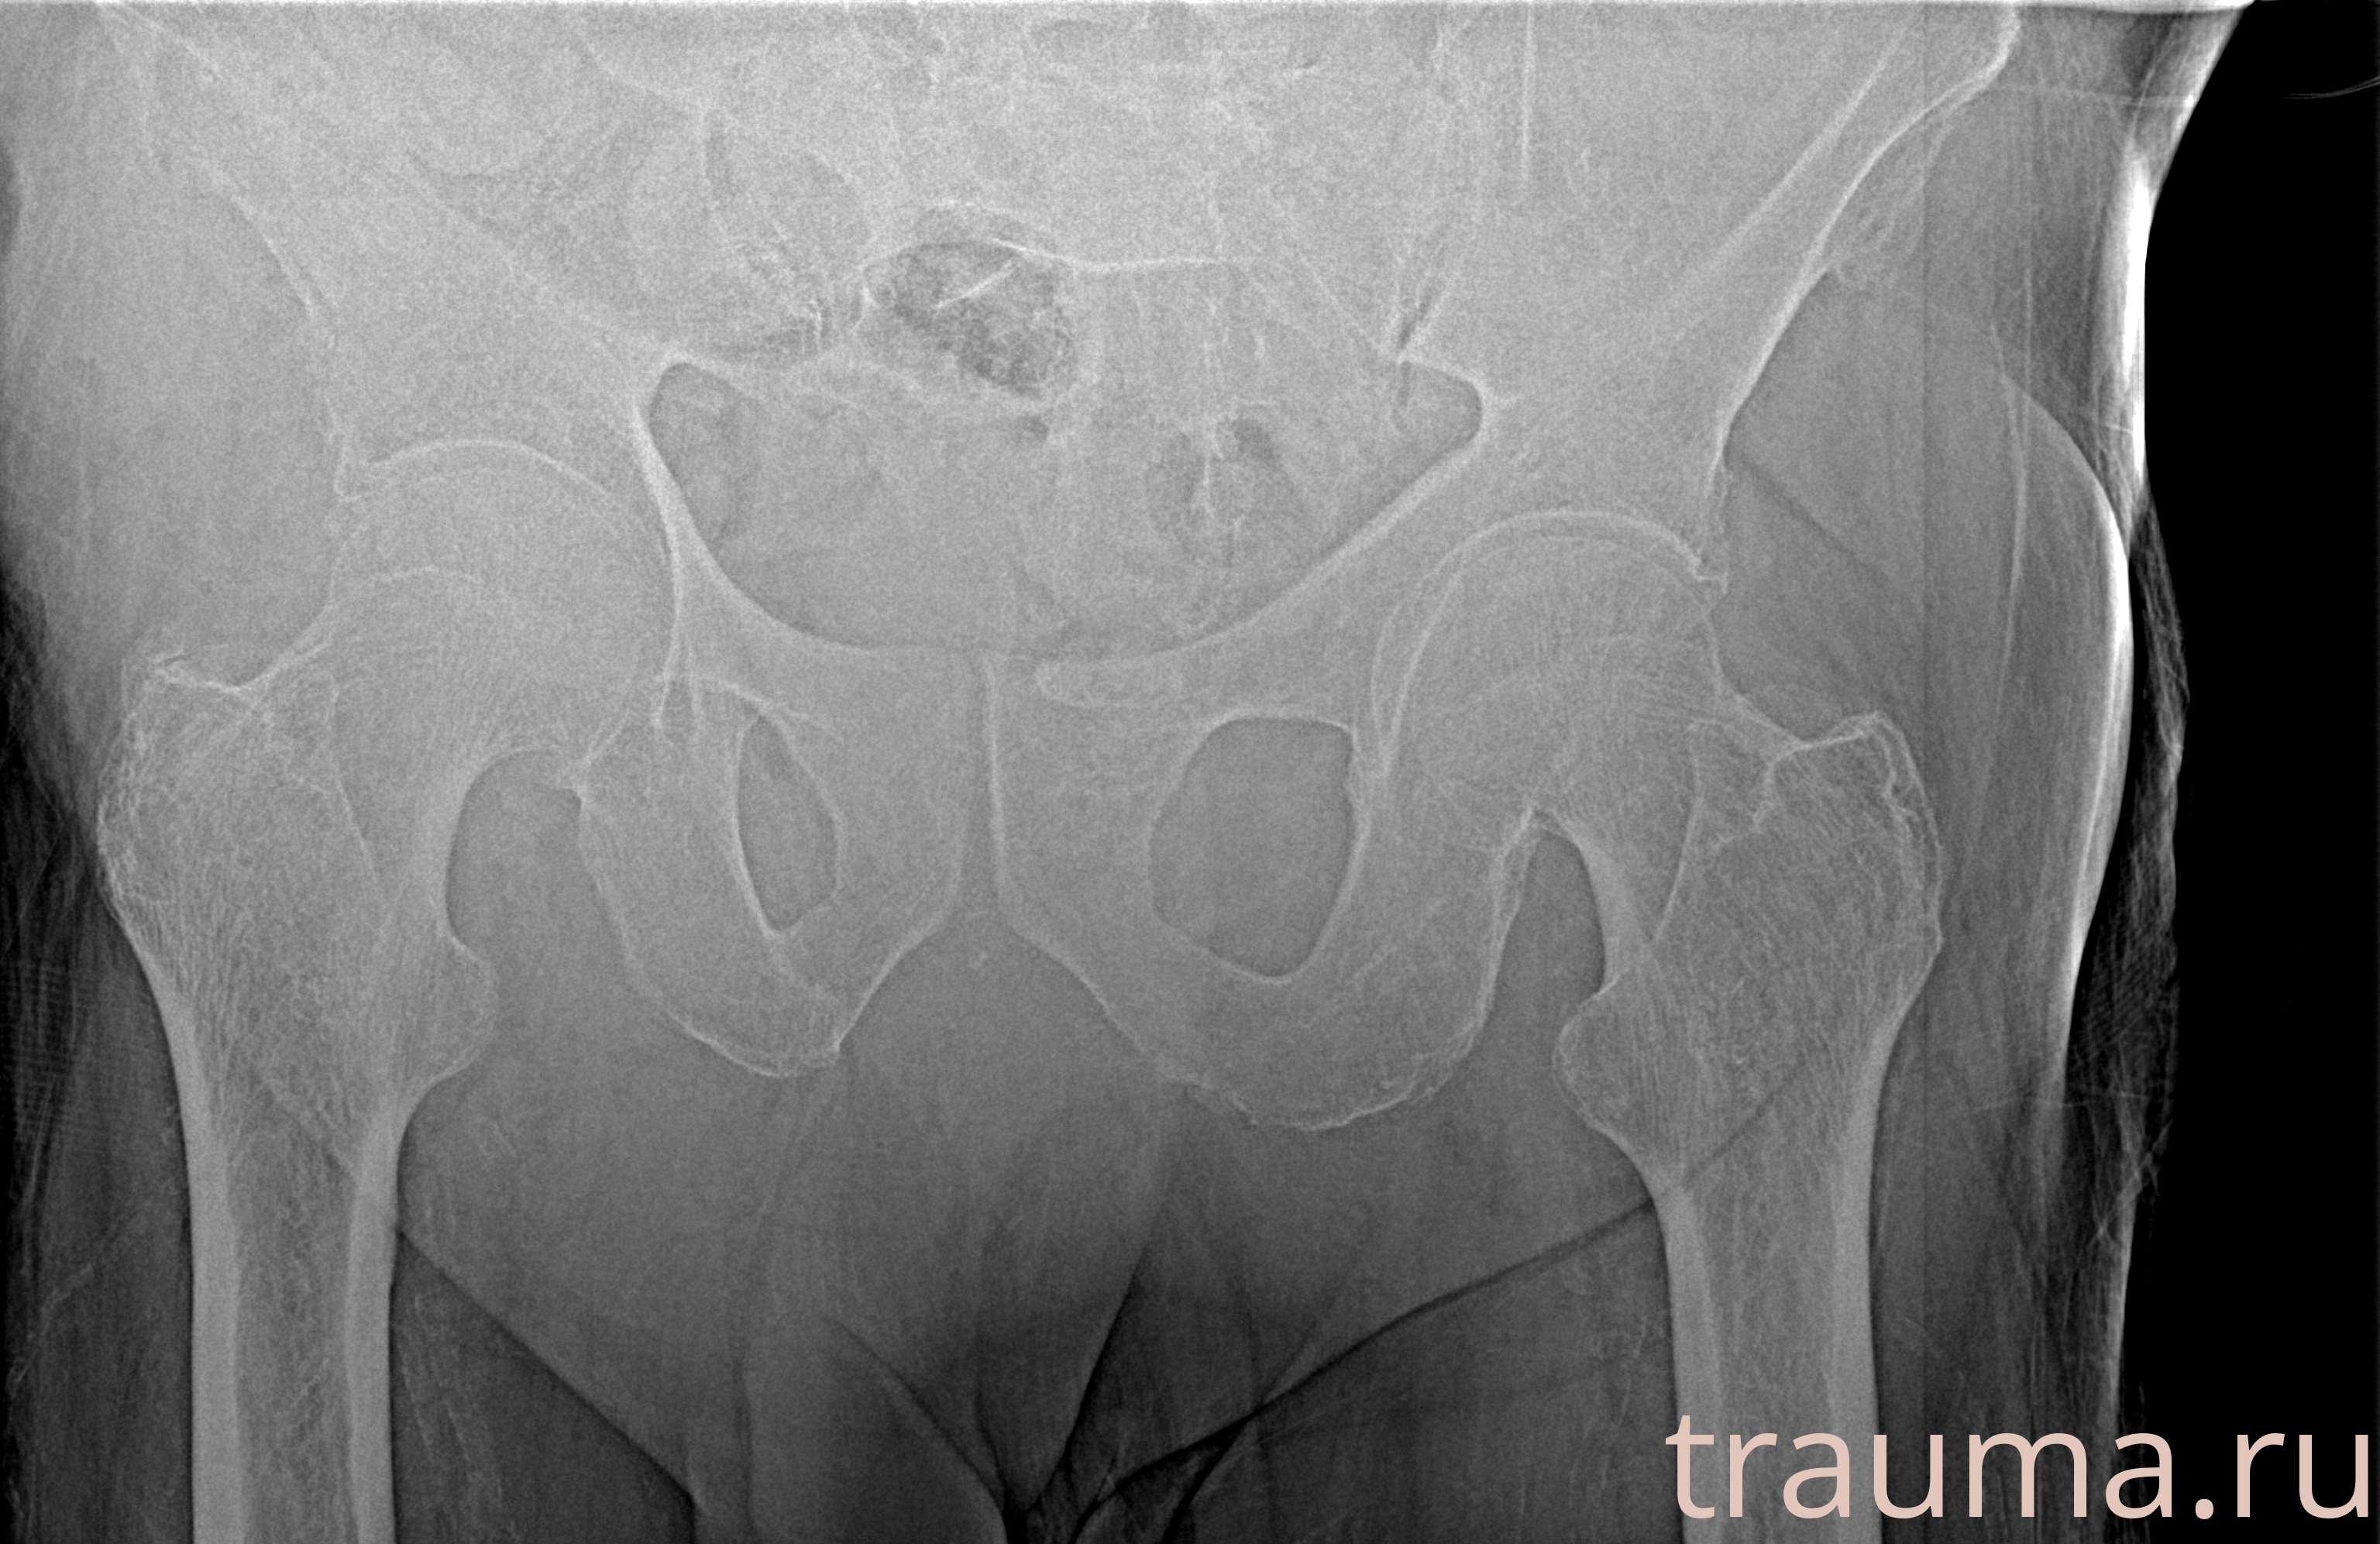

Рентгенограммы

Рентген на дому: по вашему адресу приезжает врач-рентгенолог, травматолог-ортопед с мобильным рентгеновским аппаратом, проводит диагностику травмы или заболевания, делает необходимые рентгенограммы, дает рекомендации по дальнейшему лечению. Получить качественные снимки в домашних условиях возможно благодаря уникальной методике, разработанной МосРентген Центром для института  Склифосовского